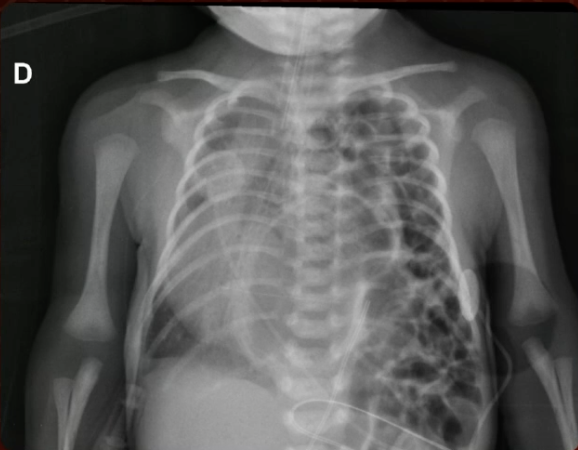

Hérnia diafragmática congênita

Qual achado no raio-x de tórax?

A

Faveolamento intratóracico + desvio mediastinal

Conteúdo abdominal no tórax